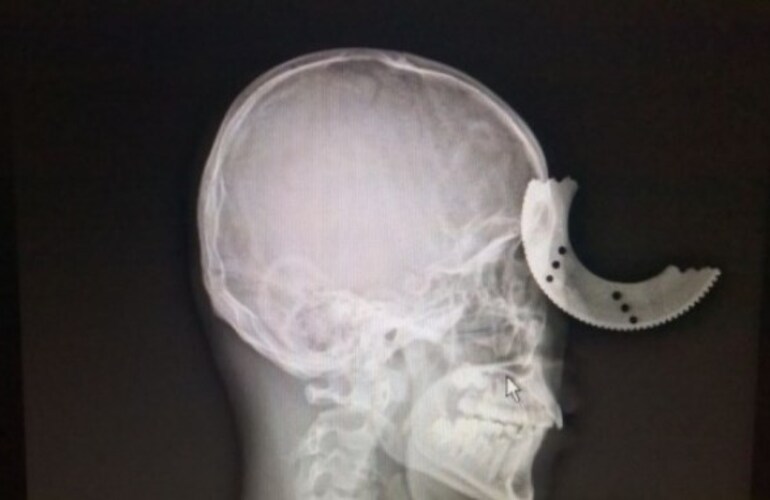

Zheng Lang, un trabajador de la provincia de Fuzhou, en China, tuvo un accidente con una sierra utilizada para cortar barras de metal, que terminó con una filosa pieza de metal incrustada en su cráneo.

Aunque el metal evitó ambos ojos, se hundió 2 centímetros dentro de su cabeza.

Zheng fue hospitalizado rápidamente y fue intervenido de emergencia para extraer la sierra, junto con fragmentos de cráneo.

Se espera que el joven se recupere totalmente, excepto por un pequeño impedimento visual en su ojo izquierdo.